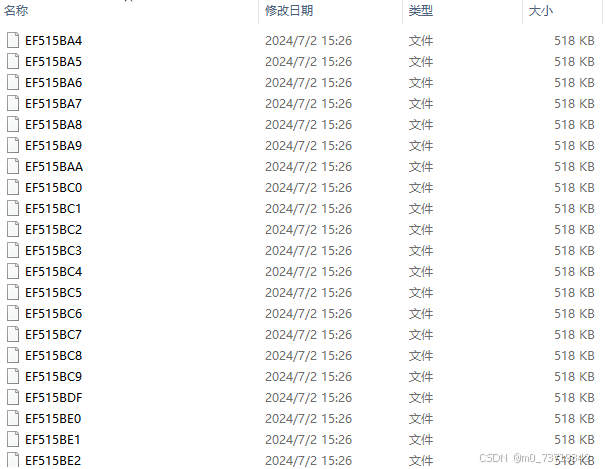

医院所提供数据源格式为ZIP/RAR格式压缩包,内含病人若干张dicom图像

如下图所示为一个病人数据的基本格式